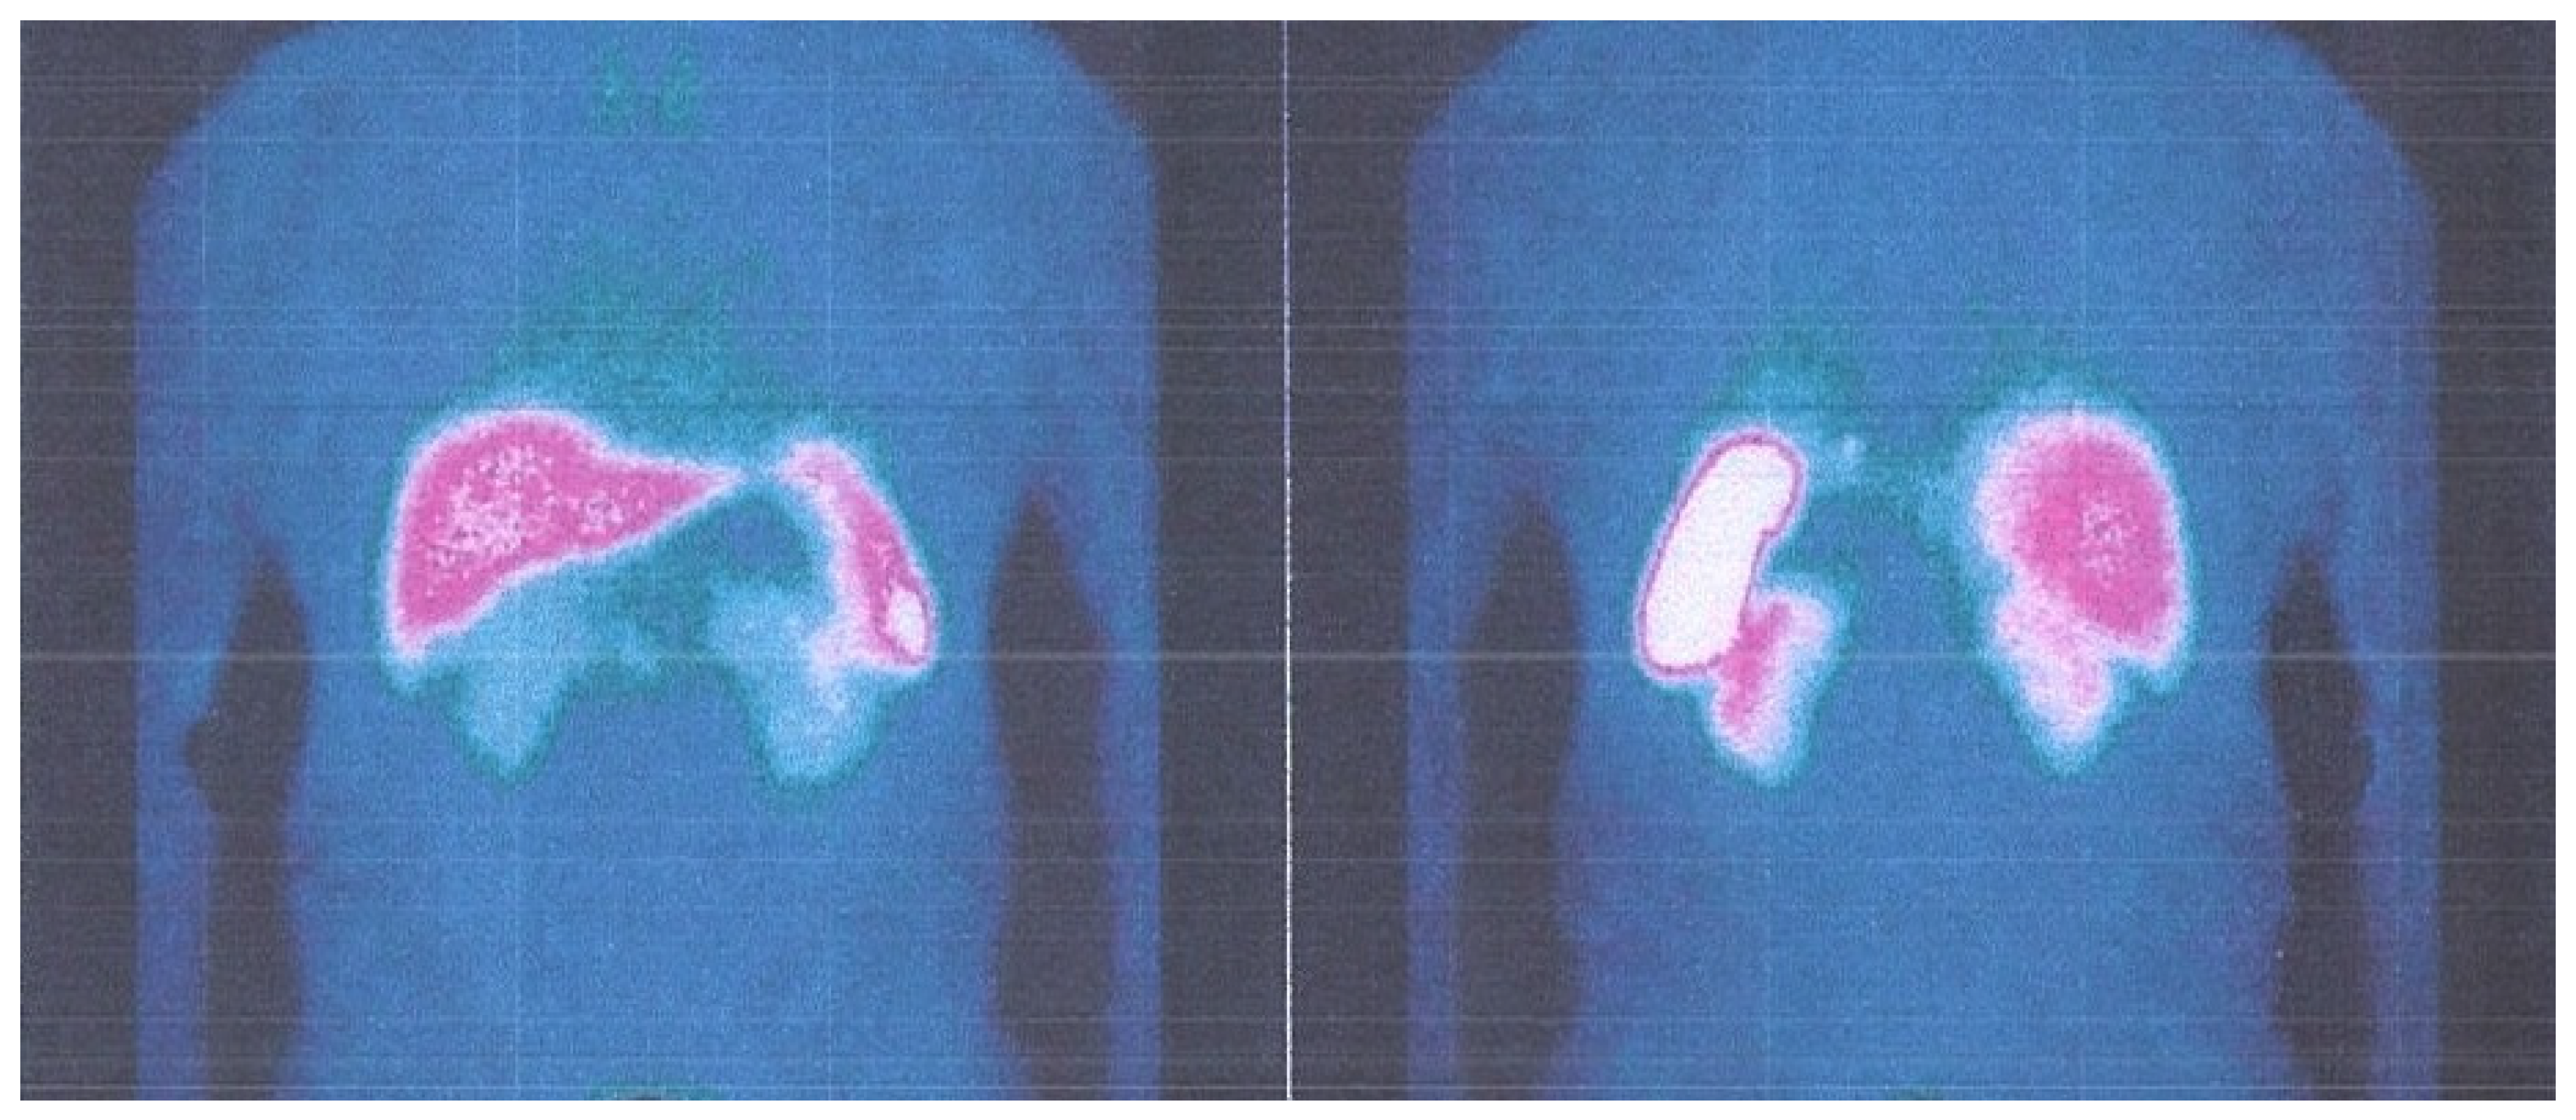

4. Case Report 3